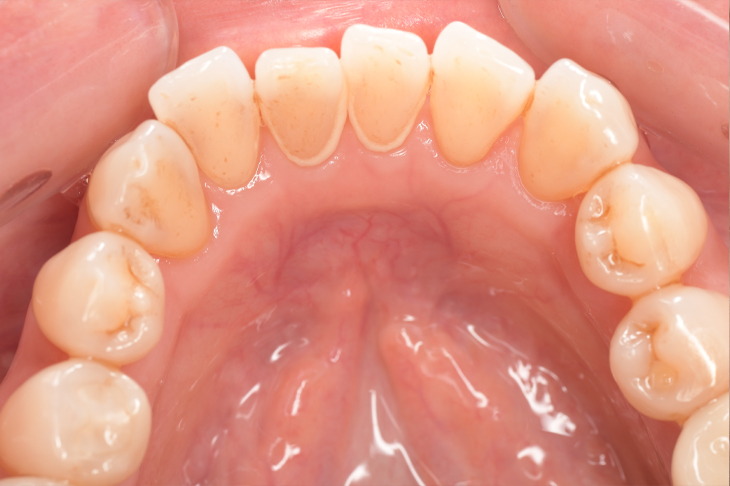

CASE 3

Before

After

基本情報

| 年齢・性別 | 30代・女性 |

|---|---|

| 主訴 | 定期検診 |

| 治療内容 | PMTC |

| 治療期間 | 60分 |

| 治療費 | 5,750円 |

| リスク・副作用 | しみる可能性があります。 |

| 治療方針 | PMTCでステインの除去。 |

| 担当者所見 | ステインが付きやすいため、3カ月毎の定期検診で除去する。 |